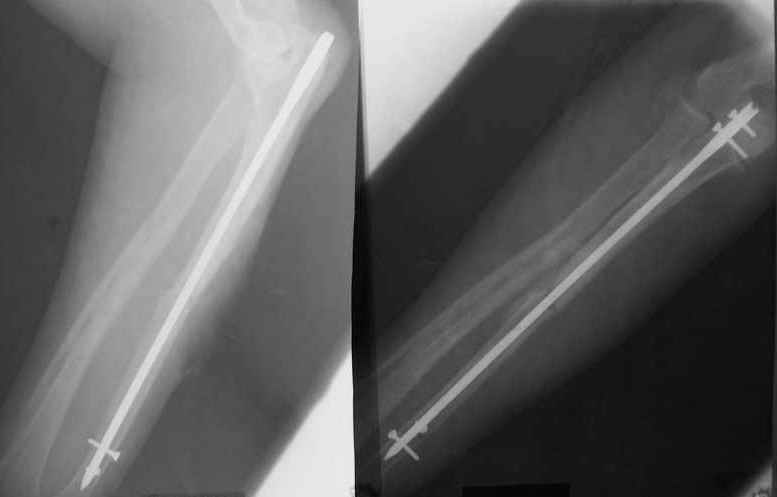

Уважаемые коллеги!Доводим до Вашего сведения наш скромный опыт применения блокирующего остеосинтеза локтевой кости (4случая), четверо пациентов с ложными суставами локтевой кости. Во всех случаях оперировали открыто с костной аутопластикой.Технических проблем введения штифтов не было. В одном случае отвалилась резьбовая часть спицы при прокс. блоке (оставлена как блокирующий винт). Дистальное блокирование осуществляли используя вместо кондуктора сп. Киршнера изгибая ее конец о край кондуктора на необходимую длину до отверстий. Наши первые впечатления классные. Очень быстрая функциональная реабилитация без гипса и консолидация через 2 мц. На представленных фотографиях двое пациентов.Тот, у которого якобы не срастается лучевая кость на АО пластине, уже катался на горн. лыжах, а сейчас опять уехал на Эльбрус -экстремал ,,,нов. С уважением Нагога Александр, ортопедическая клиника ОРТО, Самара.

А движения как раз начинаются максимально рано, на следующий день, включая ротацию - больших ран ведь нет, сильно не болит - в приложении картина в день снятия швов.

При *закрытом* интрамедуллярном остеосинтезе - это редкость. Где-то на 60 больных есть одно несращение лучевой кости (рентгенологическая находка, клинических проявлений нет) - синтез получился с удлинением.